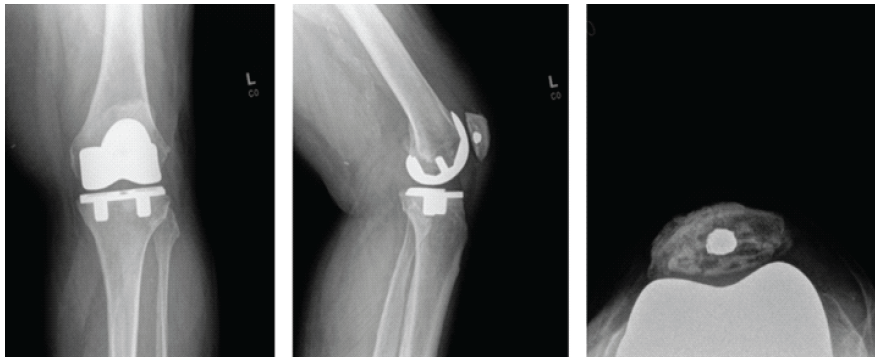

The patient arrived at the hospital for his revision surgery and was prepared with routine perioperative procedures. After induction of anesthesia, he was prepped and draped in a sterile fashion. The patient’s previous midline incision was incised, and a medial parapatellar arthrotomy was performed. The soft tissue was elevated from the lateral knee to allow for eversion of the patella, and the component was noted to be grossly loose. Fibrous scarring was removed from the undersurface of the extensor mechanism to remove the polyethylene component. The central peg of the patellar component appeared well fixed within the patellar bone. There was metallosis noted in the synovium for which a synovectomy was performed. Changing the polyethylene was discussed. However, due to the patient’s vasculopathy, the goals to minimize dissection, bleeding, and the time of the surgery were prioritized. The polyethylene was not exchanged. As the other components appeared well fixed, balanced, and in place, only the patella was of concern. A freshening cut was made to flatten the patella and reveal fresh bone. A three-peg clamp was used to place three holes that surrounded the previous peg component (Fig. 4). The well-fixed broken peg was not removed to decrease unnecessary bone loss.

Figure 4: Post-operative X-rays after revision. Three radiographic views of the left knee are visualized on the patient’s post-operative visit, including anteroposterior, lateral, and patellofemoral views, respectively. These radiographs demonstrate the original press-fit total knee arthroplasty in position, with no loosening. The retained trabecular metal peg is appreciated within the patella.

After, cement was placed under the cut surface of the bone as well as on the backside surface of the implant. The patella was then clamped in place, and any extraneous cement was removed. The patella was then held in place until the cement was fully cured. It was ensured that the knee had a centrally tracking patella and was balanced in both flexion and extension. The patient’s incision was sutured closed appropriately, and a PRINEO dressing was applied. A post-operative X-ray showed the knee to be in good alignment. The patient was then taken to the PACU in good condition, having tolerated the procedure well. Since the surgery, the patient has been progressing routinely and describes being generally happier with his knee. The patient was last seen in February 2025. At this time, they report a positive response to treatment with satisfactory progress. Multiple attempts have been made to contact the patient to schedule an additional follow-up appointment 1 year after his last visit in 2025; however, these efforts have been unsuccessful to date. At the time of the past appointment, post-operative radiographs and physical exams all demonstrate appropriate alignment without evidence of complication (Fig. 4).